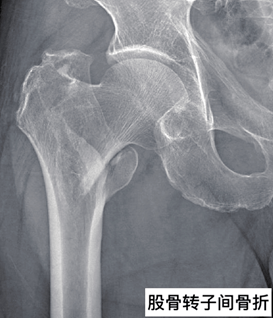

生活中意外时时发生,很多都是不能避免的,比如骨折就极为常见。俗话说伤筋动骨一百天,可见骨折的严重程度比较大,除了积极治疗之外还要多注意饮食,多吃一些蛋白质含量高的食物,像骨头汤、鸡汤等都是不错的选择。